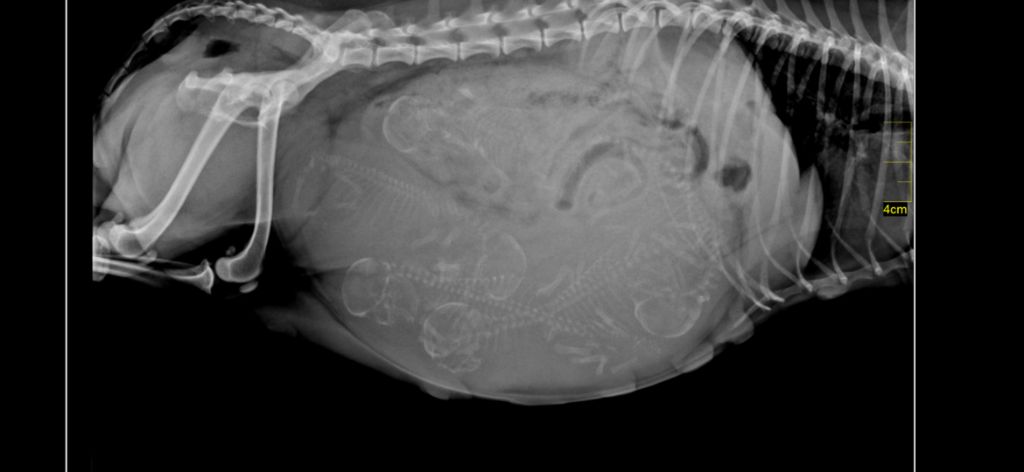

Tous nos chiens sont dépistés et testés tares oculaires, cardiaques, rotules, EF, CC, DE, ADN avec filiation